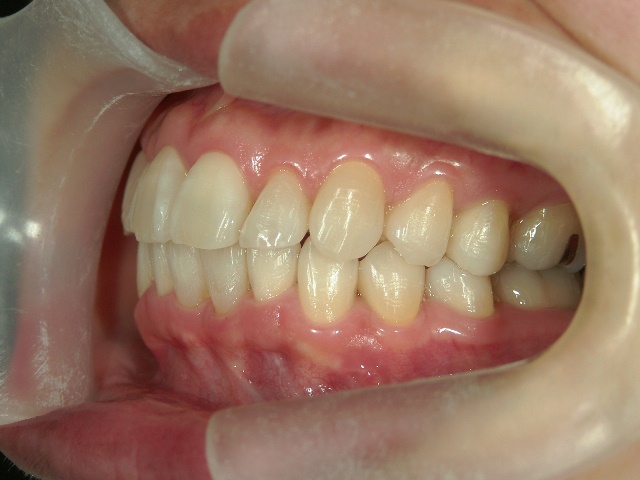

矯正歯科 治療後矯正歯科 プチワイヤー矯正 治療後矯正歯科(プチワイヤー矯正)治療後

no.41_8994_治療後_右.JPGno.41_8994_治療後_正面.JPGno.41_8994_治療後_左.JPG

矯正歯科 治療後 ミニインプラントを2本埋入し、下顎前歯を圧下